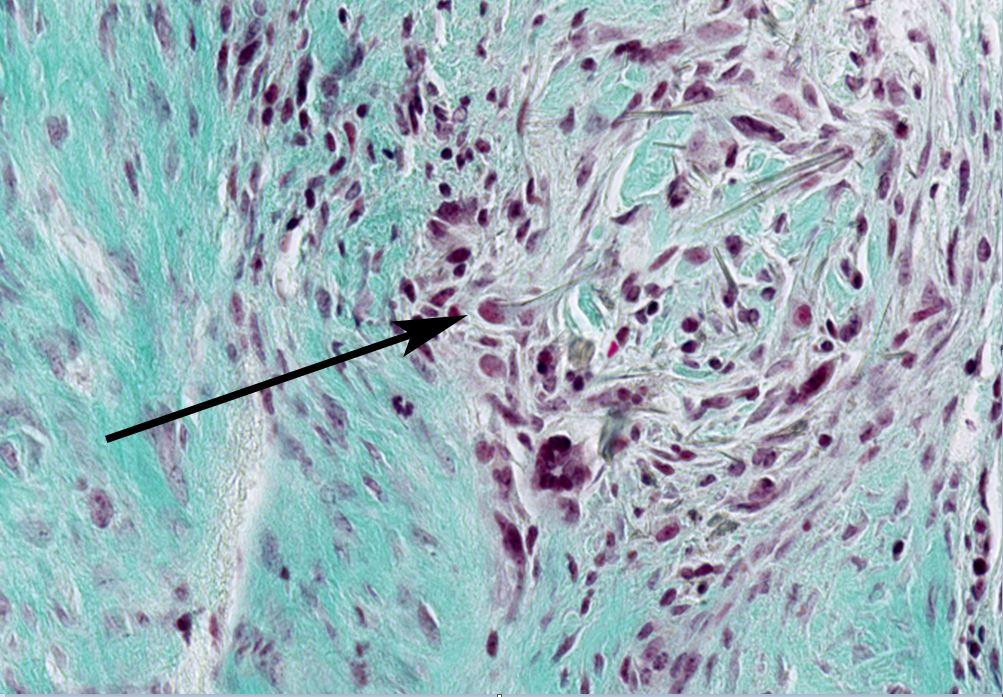

Immagine al microscopio di una fibra di amianto incastrata nella pleura

Le fibre di amianto rimangono incastrate nelle pleura dove provocano in continuazione delle microlesioni. FNS

L’amianto non è chimicamente cancerogeno. A renderlo pericoloso sono le dimensioni e la forma allungata e appuntita delle sue fibre che, una vota inalate, si incastrano nel mesotelio (membrana che ricopre diversi organi. Quella che attornia i polmoni è chiamata pleura).

Troppo grandi per essere eliminate, feriscono in modo ripetuto i tessuti. A questo punto il sistema immunitario interviene su due fronti: la difesa (cioè la distruzione delle cellule danneggiate o “difettose”) e la riparazione (la generazione di nuovi tessuti).